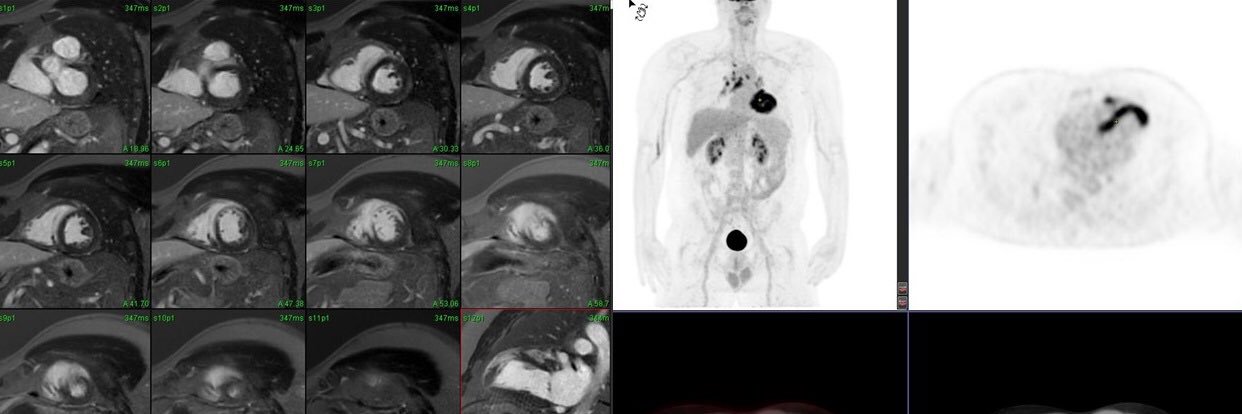

Director of Cardiovascular Imaging @ Atlantic Health System , Multimodality imager, Prof of Med, Thomas Jeff University